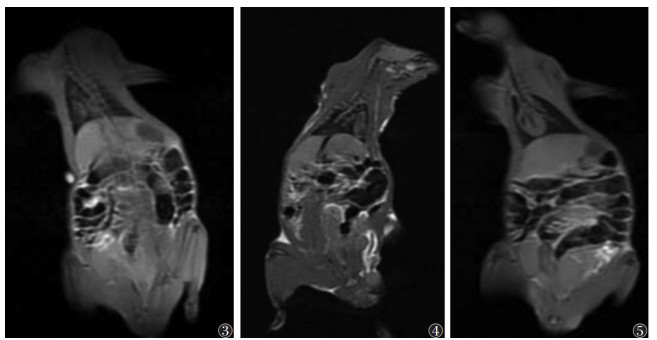

对照组、假手术组及模型组大鼠12周常规T1WI未见明显异常,肝脏表面光滑,实质信号均匀,肝叶比例协调(图 3~5);各组随机抽取9只,纳入数据分析。各组大鼠ADC值比较见表 1,图 6~8。对照组与假手术组各亚组ADC值比较,差异均无统计学意义(均P > 0.05);模型组各亚组ADC值均低于对照组及假手术组各亚组,差异均有统计学意义(均P < 0.05)。两两比较,模型组4周亚组及8周亚组均低于对照组及同一时间点的假手术亚组。模型组内ADC值随下腔静脉结扎时间延长呈先下降后升高趋势,1周亚组高于4、8周亚组,4周亚组低于12周亚组,差异均有统计学意义(均P < 0.05),ADC值在4周亚组最低(表 1)。

| 注:肝脏表面光滑,肝叶比例协调,实质信号均匀 图 3~5 对照组、假手术组和模型组大鼠12周肝脏T1WI冠状位图 |